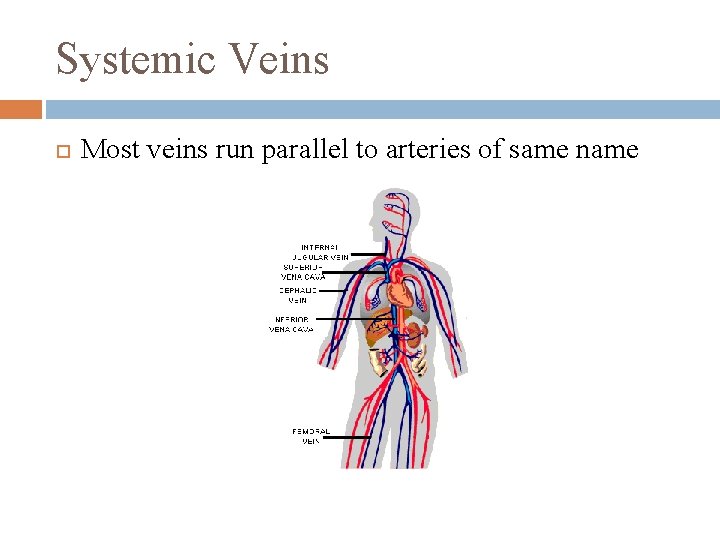

Systemic Veins Most veins run parallel to arteries of same name